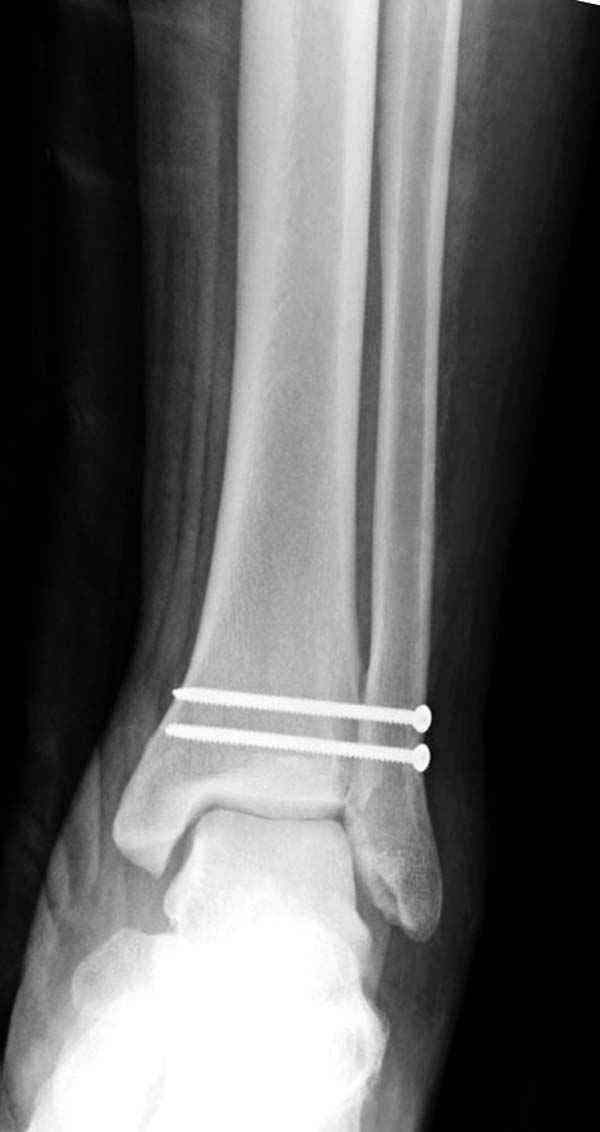

Достаточно быстрое восстановление функции.В октябре 2009г-почувствовала боль,в области рубца над гайкой открылся свищ.На Р-граммах-консолидация переломов и смещение гайки по стяжке.10.11.2009г-конструкции удалены,санация,заживление ран.В настоящее время пациентку ничего не беспокоит.На операции-раскручивание гайки-болталась на конце стяжки.Вопросы:какой механизм раскручивания и что я неправильно сделал?Свои версии:1)в области синдесмоза успела образоваться рубцовая ткань,которая при движении в суставе"пружинила",поскольку голеностопный сустав является спиральным, то и биомеханика подобна кривошипному механизму.2)Реконструктивная пластина не "реконструировалась" по форме лодыжки.Наложил,как есть.То есть подпружинивала сама пластина.Ну,это мои догадки.Что нужно,чтобы избегать впредь таких,пусть и не "страшных"осложнений:Рассверливать через лодыжку область синдесмоза?Ставить шайбу-гровер?Тщательно моделировать пластину?Прилагаю сравнительные снимки-сразу после операции и перед удалением конструкции.

Визуально никаких вопросов по репозиции не было.Да и на основании чего сомнения,что наружная лодыжка не полностью репонирована или прорезалась проволка ???Я не вижу...Снимок после репозиции справа.

Раз ,есть желание посмотреть другую проекцию выкладываю-ну лучшего качества нет...